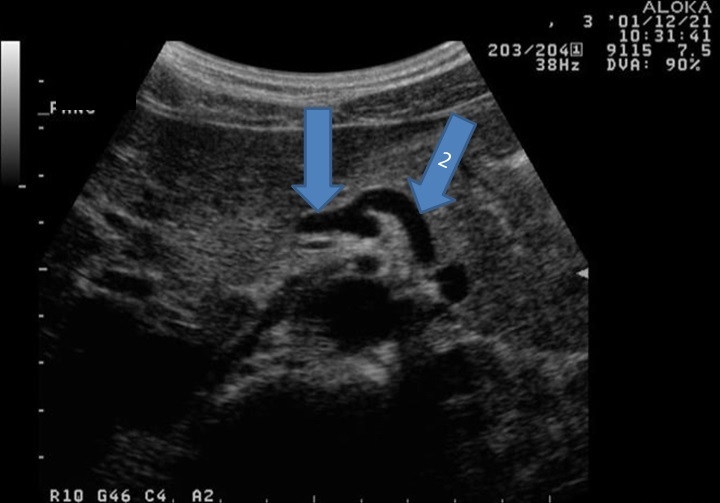

9

From left to right label the structures

A

1. Right portal vein

2. IVC